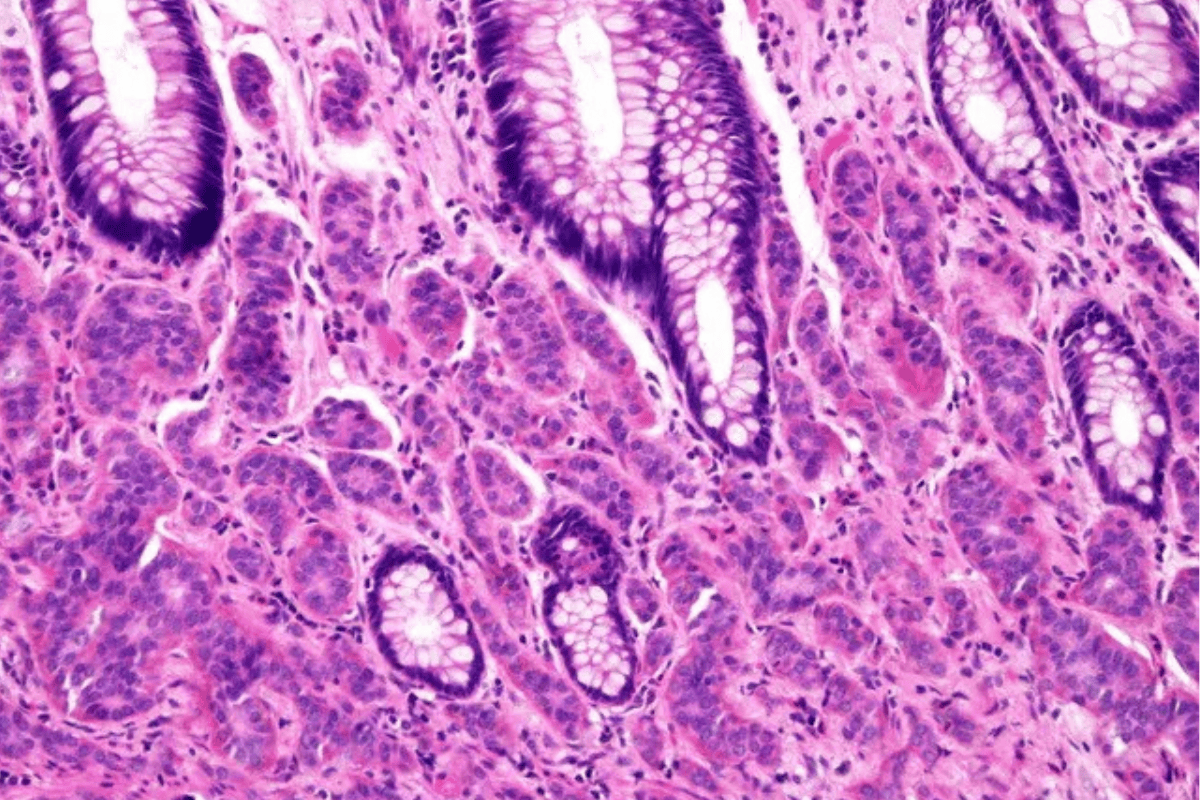

Colon Cancer Diet: Nutritional Tips, Top Foods & Meal Plans